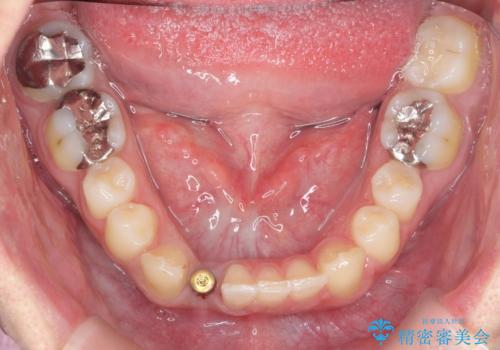

下の前歯のインプラント 生まれつき歯が少ない

- 下の前歯が1本生まれつき少なかったため、インプラント治療を行いました。

インプラントの前に矯正治療を行い、入れる隙間を確保しました。

ブリッジにすることも可能でしたが、両側の歯が天然歯であること、また、事前に矯正で噛み合わせを整え、幅も確保していたこと、CTにより骨の厚みがある程度あったことを踏まえ、インプラントも可能であるとお話しし、選んでいただきました。

唇側の骨増成もしっかり行い、前歯部インプラントによくある、歯茎が下がって見えることもない、審美的なインプラント補綴ができました。